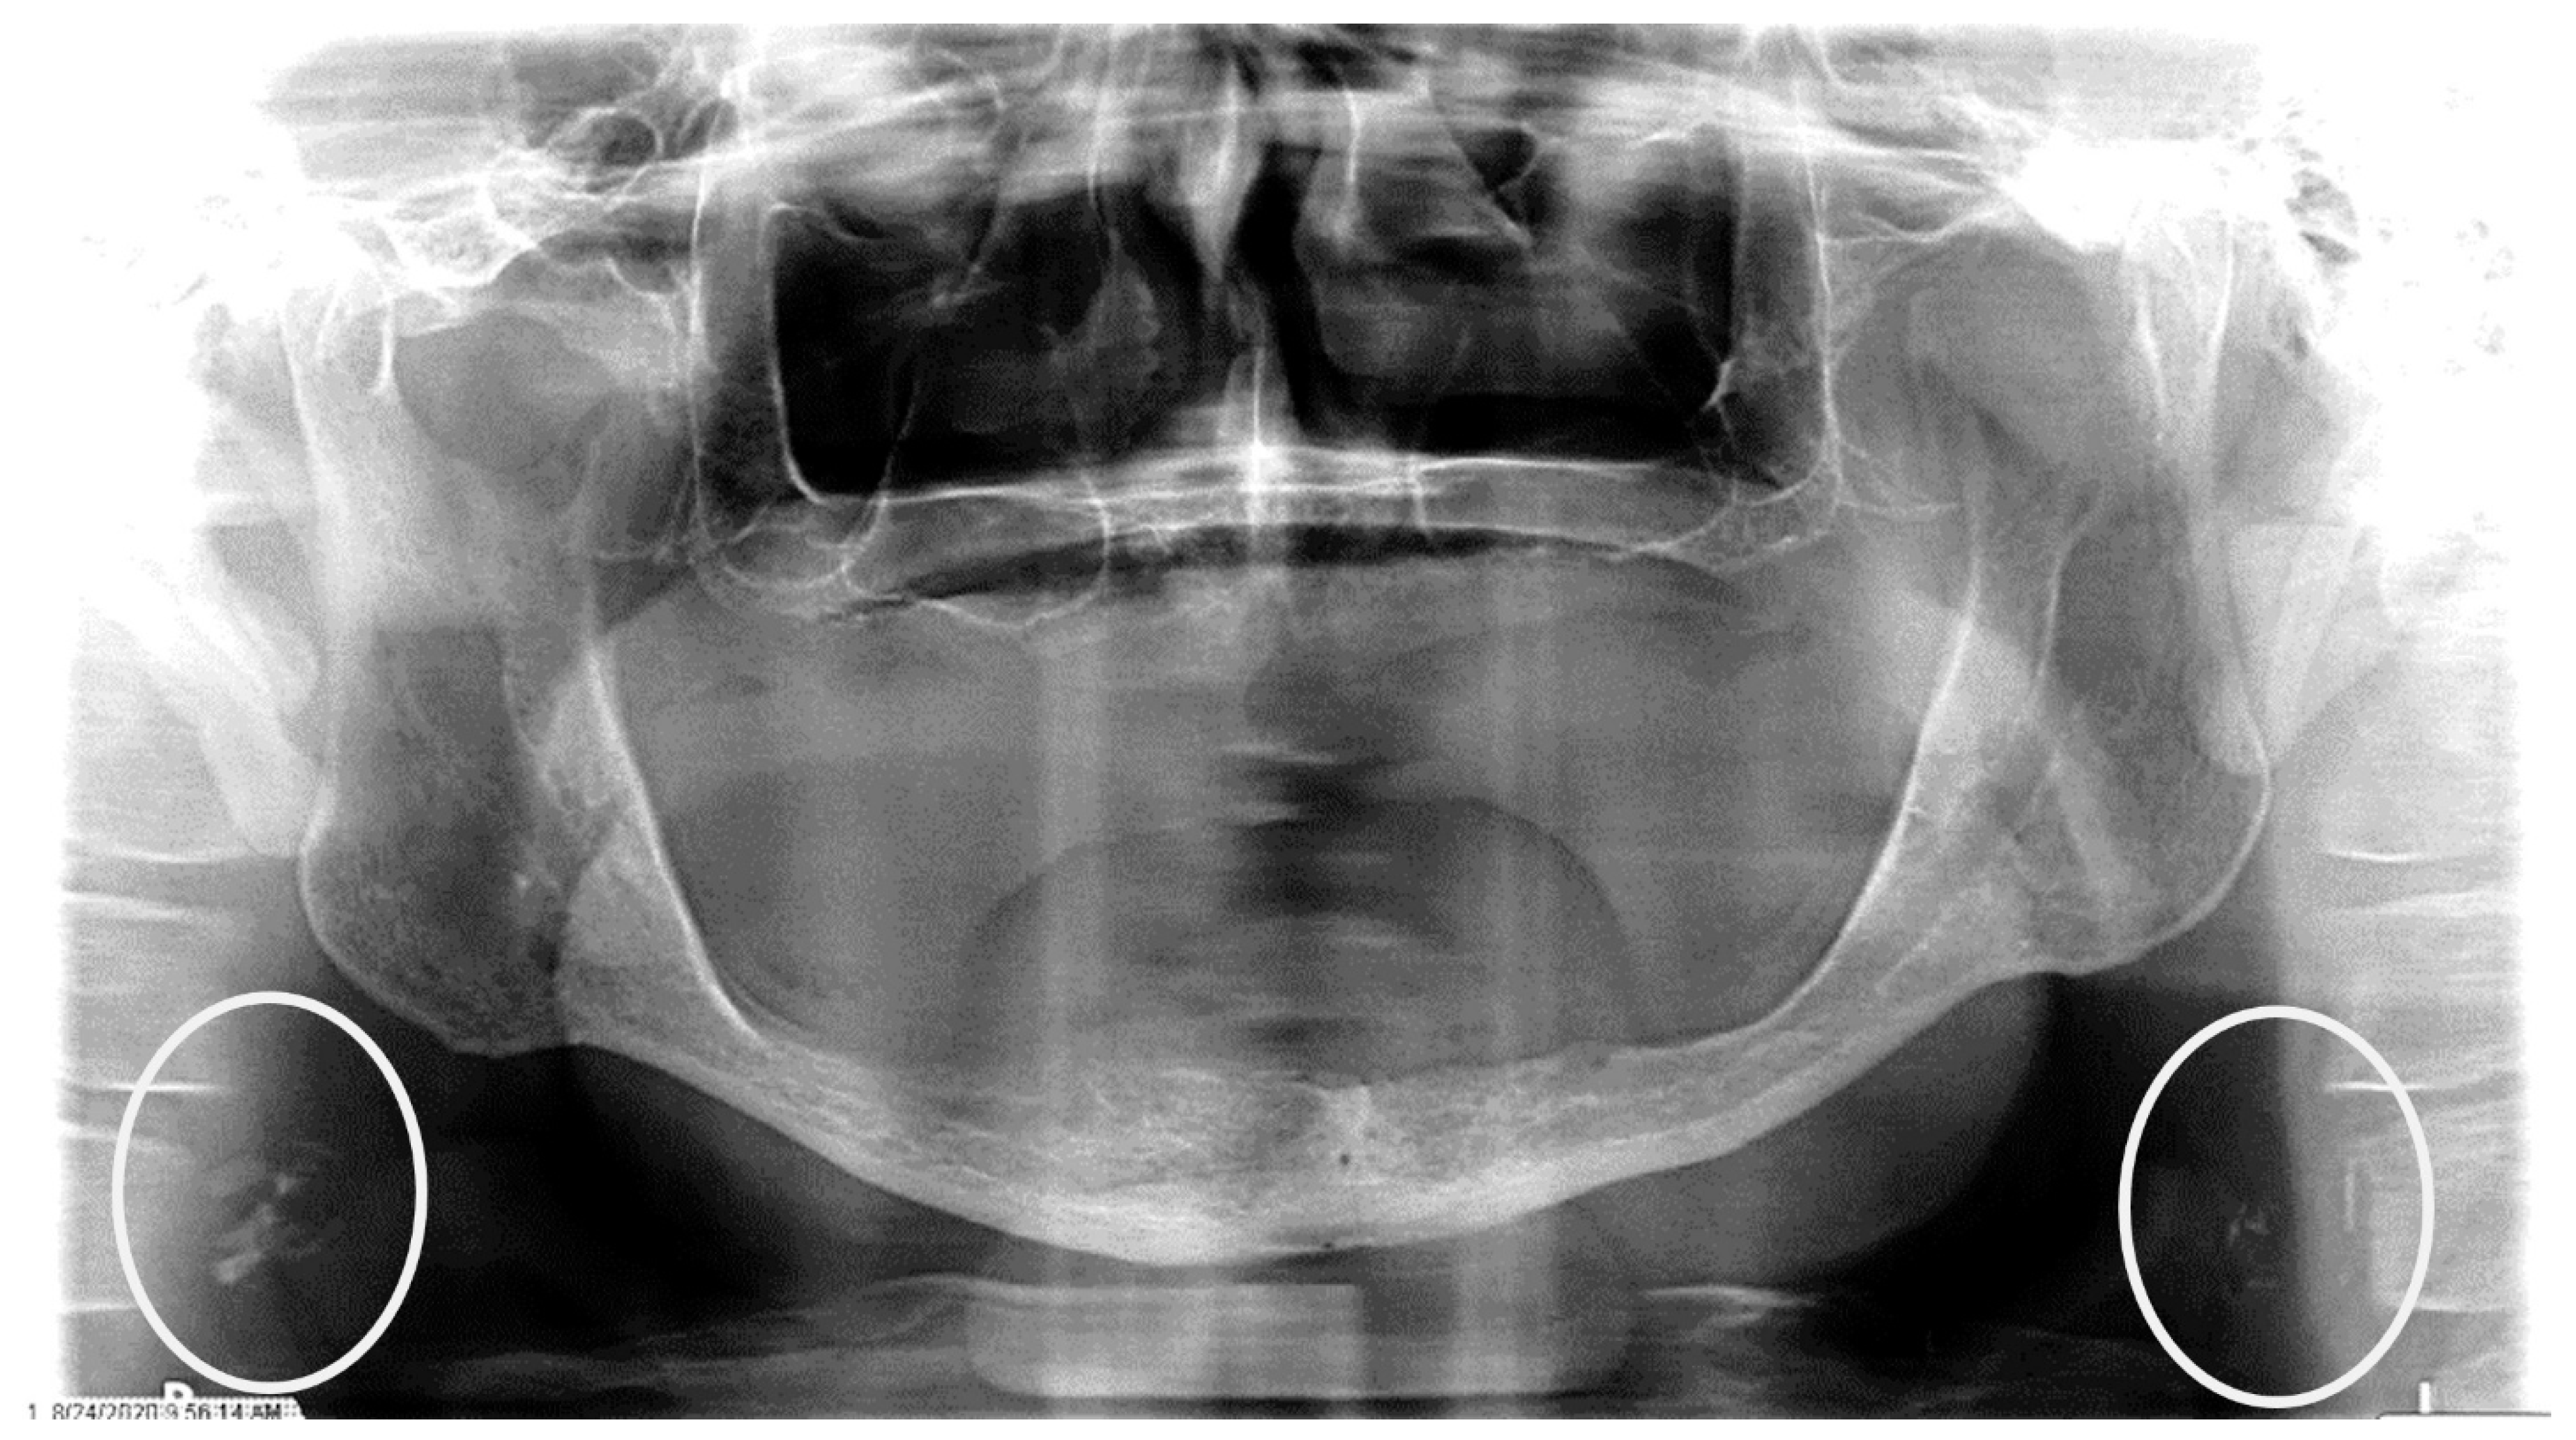

The characteristics of the CAC patients are presented in Table 1. Between 2014 and 2023, there were 559 patient records with the terms “carotid artery calcification” or “carotid” or “calcification of the carotid artery” noted. After the panoramic radiographs were reviewed, 314 patients were confirmed to have a diagnosis of CAC (including 26 patients with a history of carotid endarterectomy). The remaining 245 patient records were excluded because of the absence of detectable CAC on PRs and the absence of PRs to review. The ages ranged from 29 to 92 years, with a median of 68 years. CAC was most prevalent (39.5%) in the seventh decade of life. There were 168 (53.5%) female and 146 (46.5%) male patients. The median age of the female patients was 68 years, and the median age of the male patients was 69.5 years. The calcifications were identified unilaterally in 168 (53.5%) patients (88 females/80 males; mean age: 67.8 years) (Figure 1 and Figure 2) and bilaterally in 146 (46.5%) patients (80 females/66 males; mean age: 68.6 years) (Figure 3, Figure 4 and Figure 5). The DMFT index in the CAC patients ranged from 8 to 32 (mean = 26.6). The frequency of patients with CAC with a history of hypertension, hyperlipidemia, diabetes mellitus, CVA, and CAD was 86.2%, 57.6%, 30.7%, 15.5%, and 28.7%, respectively.

Figure 3.

The panoramic radiograph of an 80-year-old male patient with a medical history of hyperlipidemia and diabetes mellitus showing bilateral carotid artery calcifications (CACs) during a comprehensive dental examination. The CACs are encircled by a white line.